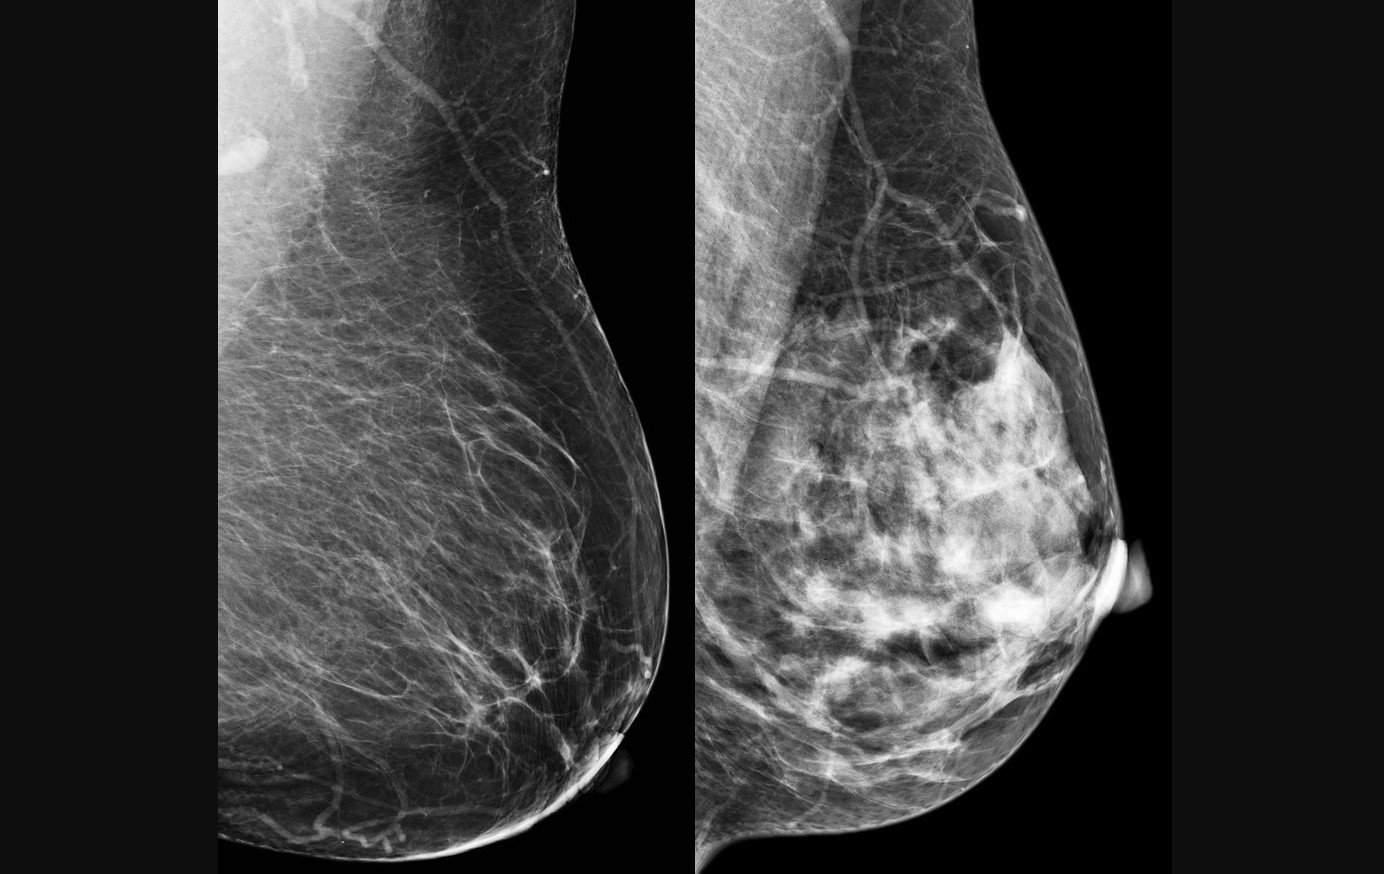

O câncer de mama foi escolhido como alvo para teste do modelo computacional porque é o tipo mais comum entre mulheres no mundo, com 2,3 milhões de casos e 670 mil mortes registradas em 2022 (imagem: CDC/reprodução)

O câncer de mama foi escolhido como alvo para teste do modelo computacional porque é o tipo mais comum entre mulheres no mundo, com 2,3 milhões de casos e 670 mil mortes registradas em 2022. A detecção precoce é crucial para aumentar as chances de cura e sobrevida. No entanto, métodos tradicionais, como a mamografia, dependem fortemente da interpretação humana, o que pode levar a variações no diagnóstico. “Apesar de ser teoricamente simples de acompanhar, a mamografia ainda é um exame cuja interpretação depende muito do profissional que realiza o procedimento”, diz Papa.

No estudo, as informações codificadas nos qubits foram pixels das imagens de mamografia e ultrassonografia. Às vezes, um pixel apenas; às vezes, mais de um. O modelo foi testado com duas bases de dados: BreastMNIST (com imagens de ultrassonografia) e BCDR (com mamografias segmentadas). Mesmo utilizando um circuito com apenas quatro qubits, a rede híbrida obteve desempenho competitivo. No melhor caso, alcançou 87,2% de acurácia no conjunto de teste e 86,1% no de validação. “A ideia foi criar uma arquitetura que poderá ser utilizada e aprofundada em outros estudos”, comenta Rodrigues.